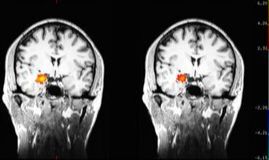

Learn more about how meditationĀ seems to change the brain in depressed patientsĀ here.